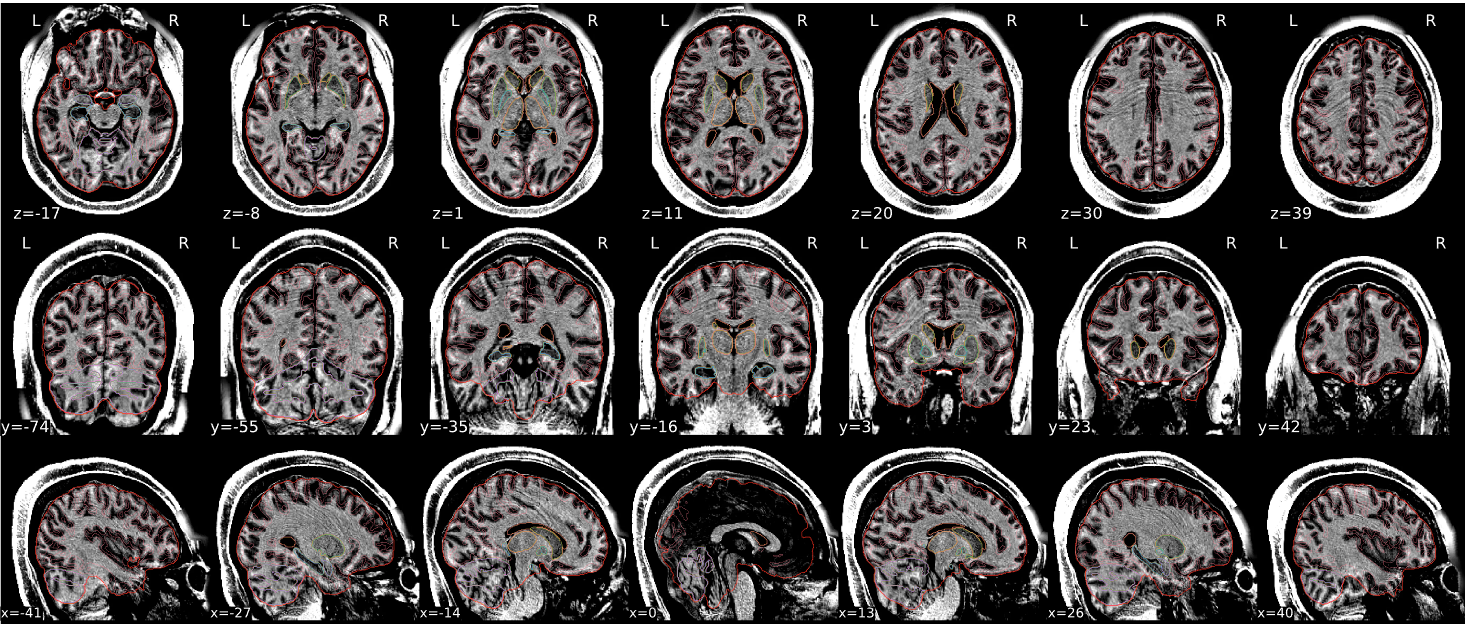

dT1w spatial normalisation

This QC step shows the registration of the T1 image to MNI space.

The registered T1 image is shown in the background with a brain atlas in MNI space as an overlay.

Example of a good subject

- If the registration performed well, you should see an overlap (i.e., correspondence of structures) between the MNI template and the T1 registered to the MNI space.

Example of a bad subject

- In case of poor registration, you should see a misalignment between the MNI template and the T1 (e.g., brain shifted down).

Summary

| good | bad |

|---|---|

| Structures of the MNI template and the registered T1 are well aligned | Structures of the MNI template and the registered T1 aren’t well aligned, e.g. brain is shifted downwards |